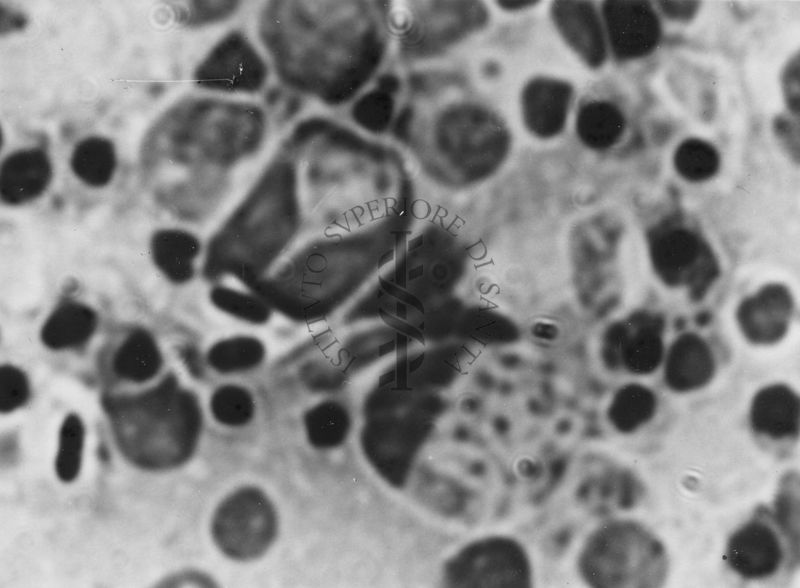

Immagini di Emoprotozoi

PAREN.00835-00841